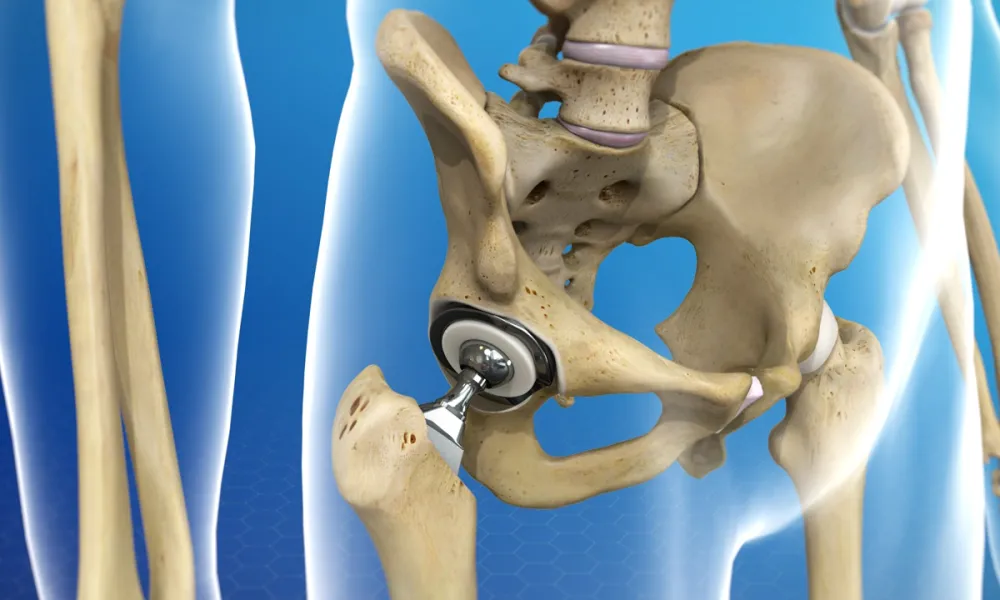

A hip replacement is a surgical procedure in which the damaged parts of the hip joint are removed and replaced with a prosthesis designed to replicate the ball‑and‑socket mechanics of a healthy hip. In a total hip arthroplasty the surgeon replaces both the femoral head (the ball) and the acetabular socket; a hemiarthroplasty replaces only the femoral head in select fracture cases. Implants are typically made from combinations of metal, ceramic, and high‑density polyethylene to provide durable, low‑friction motion. The operation is indicated when hip pain and stiffness significantly limit daily activities and conservative measures—such as medications, physical therapy, weight management, and injections—no longer provide adequate relief. Surgeons choose an approach and fixation method (cemented, uncemented, or hybrid) based on patient age, bone quality, and activity level; uncemented components rely on bone ingrowth into a porous surface, while cemented components are fixed with bone cement. The procedure usually takes one to two hours under regional or general anesthesia, and most patients begin mobilizing with physical therapy within 24 hours. Modern hip replacements can last many years, often 15 years or more, but implant longevity depends on activity, implant type, and surgical technique.

A partial hip replacement (hemiarthroplasty) replaces only the femoral head and is frequently used for certain displaced femoral‑neck fractures in older, lower‑demand patients where the socket remains healthy; it is a shorter operation with different long‑term wear considerations than total replacement.

Hip resurfacing preserves more native bone by capping the femoral head with a metal surface and pairing it with a metal socket; it has been offered to younger, active patients who want to conserve bone for potential future revisions, but it carries specific risks and is less commonly used today.